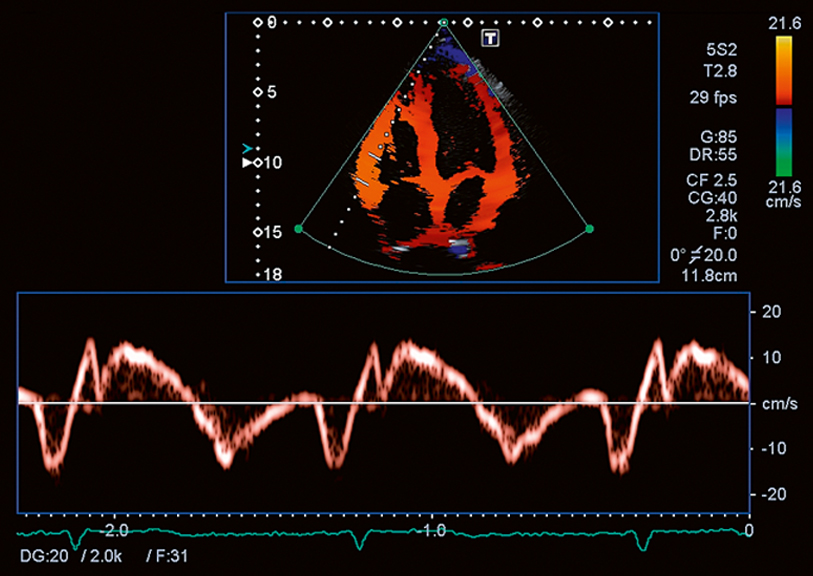

Tissue Doppler

Rapidly assess global diastolic function of the LV and RV with Pulsed-Wave TDI. Canon Medical Systems' high frame rate 2D TDI and spectral Doppler TDI provides both visual and quantitative formats for assessing global function in all your cardiac patients.